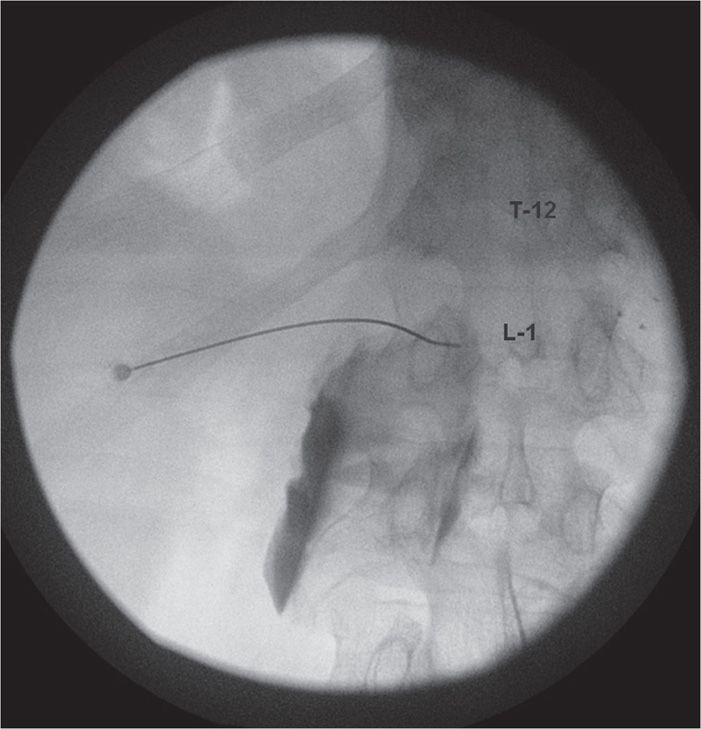

Celiac Plexus Block for Abdominal Pain Explained (602) 5076550 YouTube. The celiac plexus is comprised of three pairs of ganglia:. Change to a lateral view;

Fluoroscopic Guided Celiac Plexus/Splanchnic Nerve Block Technique and Overview The from theprocedureguide.com